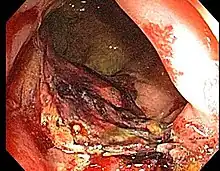

Proctitis is an inflammation of the anus and the lining of the rectum, affecting only the last 6 inches of the rectum.

Doctors can diagnose proctitis by looking inside the rectum with a proctoscope or a sigmoidoscope. A biopsy is taken, in which the doctor scrapes a tiny piece of tissue from the rectum, and this tissue is then examined by microscopy. The physician may also take a stool sample to test for infections or bacteria. If the physician suspects that the patient has Crohn's disease or ulcerative colitis, colonoscopy or barium enema X-rays are used to examine areas of the intestine.